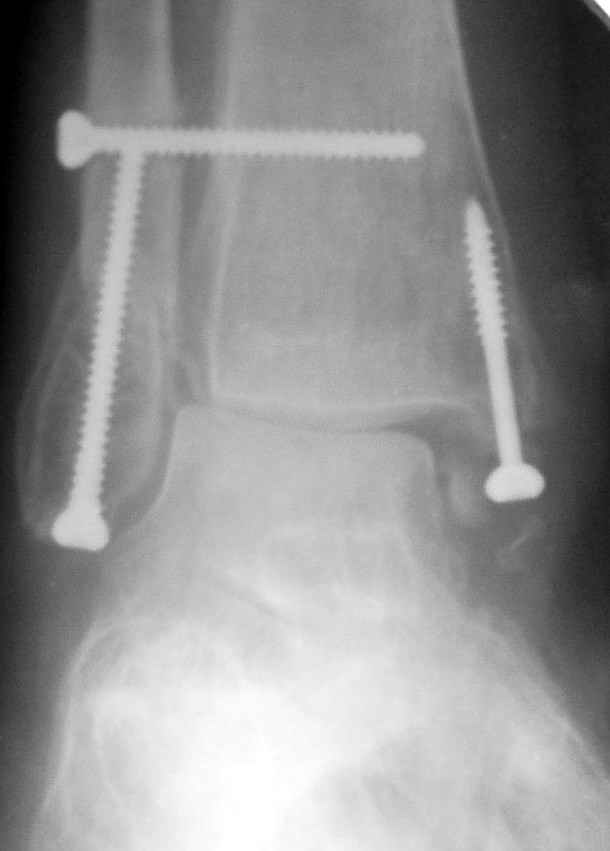

Ниже рентгенограммы

До операции 28 июля

Операция 29 июля

Через месяц

Боковой через месяц